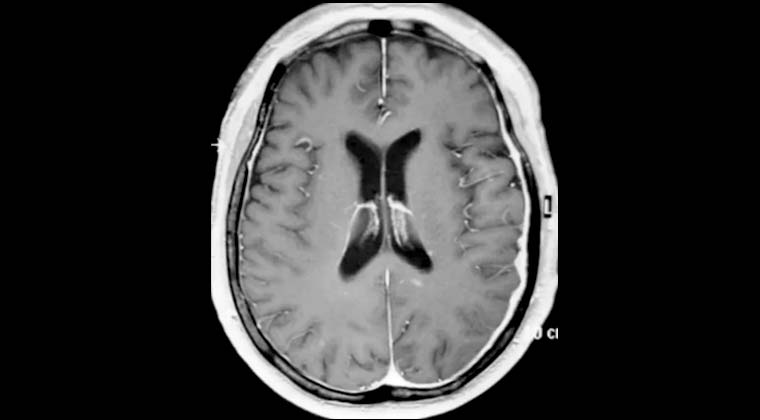

Жалобы: слабость в левой стороне тела, нарушение походки в течение 2 недель. Диагноз: множественные метастазы рака легких в головной мозг.

Рисунок 1: 25.02.2022 Планирование лечения Гамма-ножом опухоли в правой лобной доле, выраженный перифокальный отёк.

Рисунок 2: 25.02.2022 Одновременно проведено лечение Гамма-ножом опухоли в левой височной доле.

Рисунок 3: 25.07.2022, через 5 месяцев после лечения контрольное МРТ показало, что опухоль в правой лобной доле исчезла, пациентка ходит самостоятельно.

Рисунок 4: 25.07.2022, контрольная МРТ показывает, что опухоль в левой височной доле также исчезла.